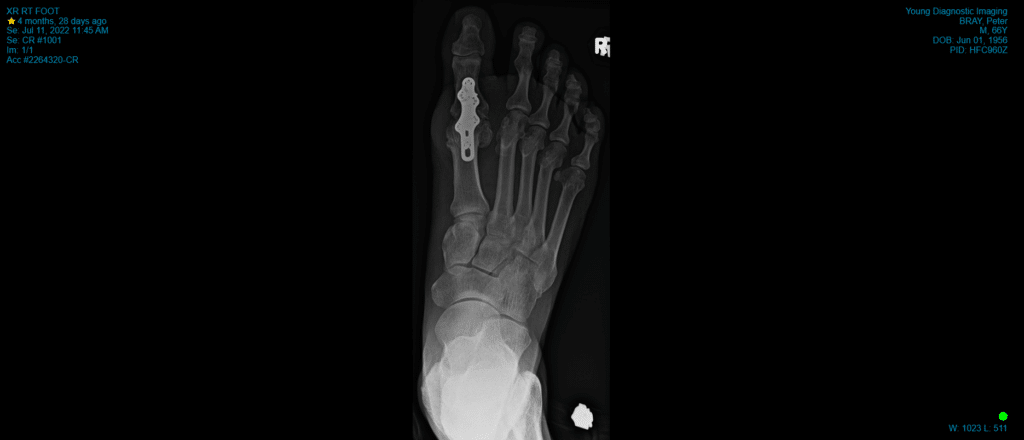

MTPJ arthrodesis (fusion)

This is the ‘gold standard’ procedure for moderate to severe arthritis. The remaining cartilage in the joint is removed, the bones on either side of the joint are fused together and held with screws in isolation or a combination of screws and a plate. 90-95% of patients will experience good pain relief with this. However, the joint is stiffened and this limits the wearing of high heels and can make running difficult. There is a small risk of developing arthritis in the next joint along the big toe but this is rarely troublesome.

Less than 5% of patients will develop a complication that may require further intervention. These include wound-healing problems, infection, damage to nerves and blood vessels, incomplete relief of symptoms, and in the case of arthrodesis, failure of the bones to knit together requiring further surgery. Recovery times and swelling also vary but can last several months. Occasionally the metal plate may require removal.